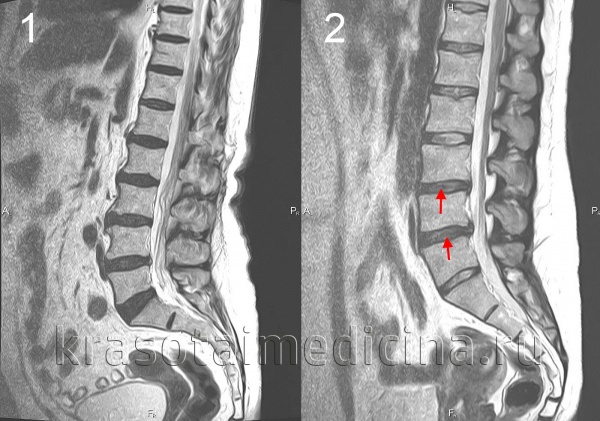

МРТ поясничного отдела позвоночника. 1- выраженная дегидратация межпозвонковых дисков во всех сегментах. 2- дегидратация в сегментах L3-L4, L4-L5 справа (разные пациенты)